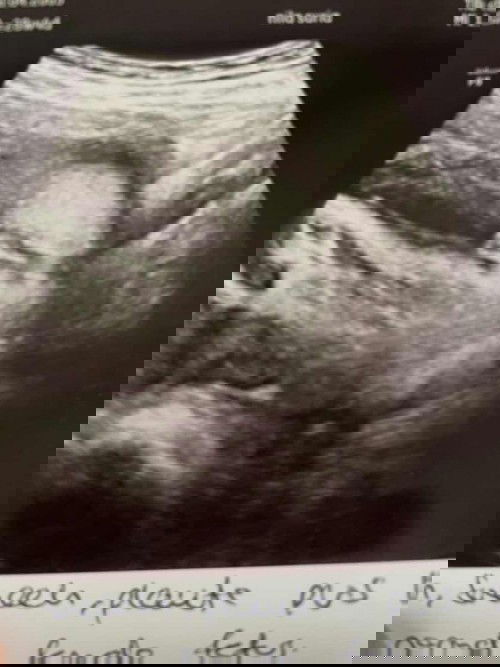

Ibu ibu ni boy ke girl

Excited to become a mum

Boy rasanya sebb nmpk cm pistol tu